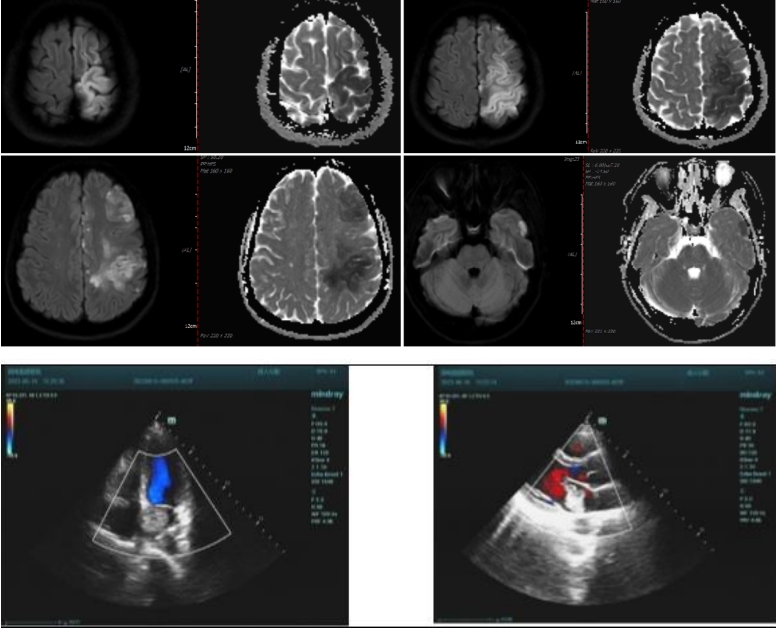

首先由神經內科辛伽倫主治醫(yī)師匯報了一例因心房粘液瘤所致急性多發(fā)性腦栓塞的青年女性病例,他就患者的臨床資料,影像學資料、檢驗資料及超聲資料等進行了詳細介紹,重點對該患者的頭顱MRI各序列影像學特點、心臟超聲表現(xiàn)進行了逐一分析,并結合國內外文獻報道對心房粘液瘤所致急性缺血性卒中的治療進行了深入探討。進而從該典型病例出發(fā),延伸總結了青年卒中的發(fā)病特點、常見病因及診療策略。

接下來,心血管內科、影像科、超聲科等多名高年資醫(yī)師分別就該例患者的頭顱MRI表現(xiàn)、心臟超聲表現(xiàn)、心房粘液瘤與卒中的關系、心源性卒中的診斷與治療、青年卒中的病因鑒別等方面從各自專業(yè)角度進行了深層次的分析,并結合該患者及青年卒中存在的問題進行了多學科交流討論,提高了此類患者診療的認識。